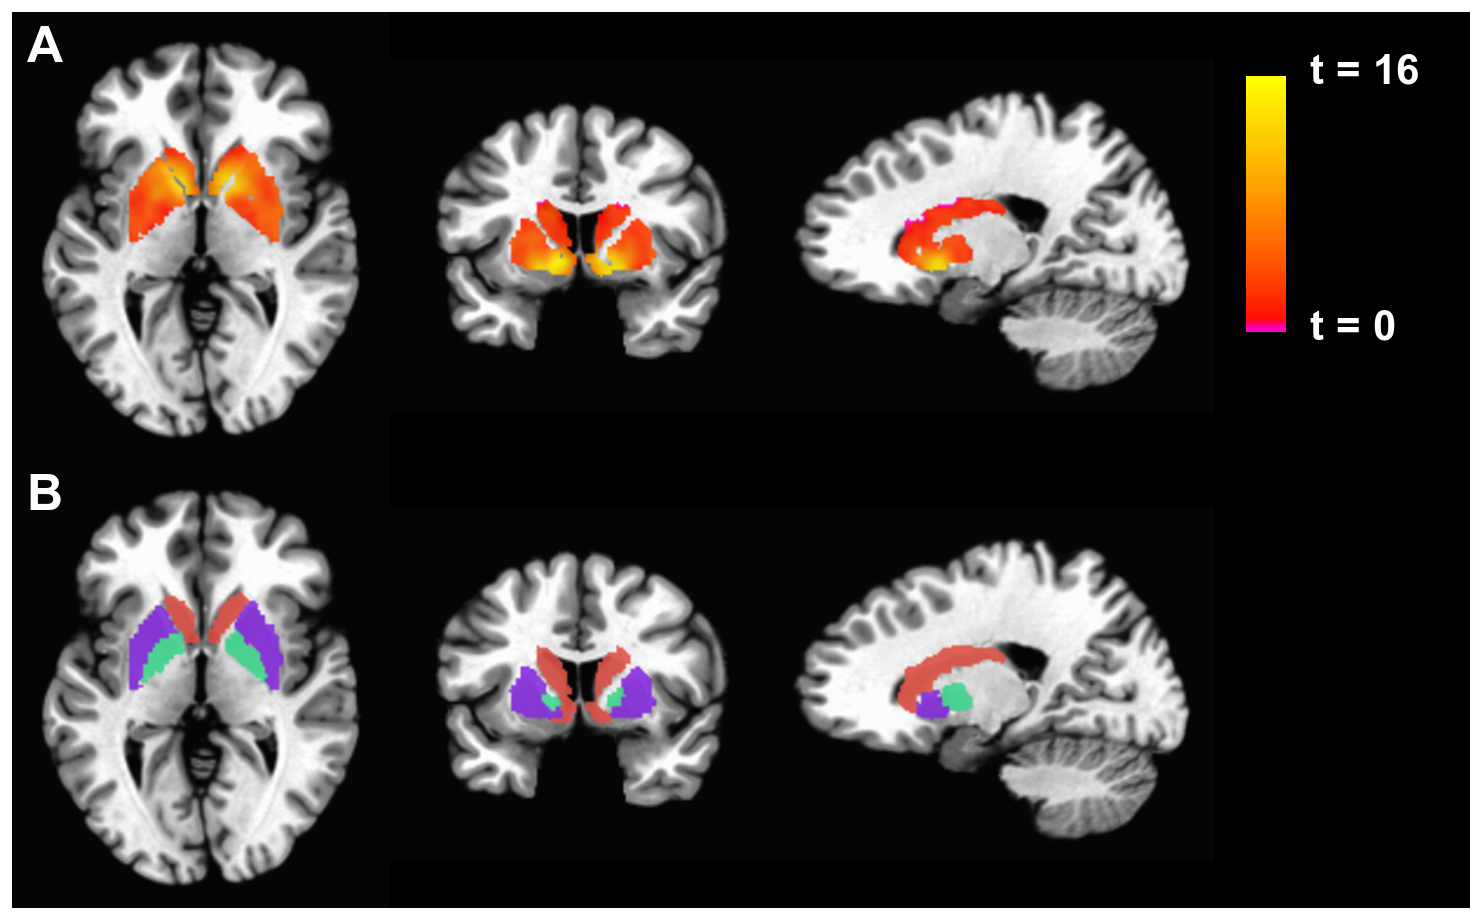

Functional MRI

Functional MRI (fMRI) is a specialised type of MRI scan that measures brain activity by detecting changes in blood flow using the blood-oxygen-level-dependent (BOLD) contrast technique7,8. It enables the non-invasive observation of brain function and connectivity and is used to study brain function in various neurological and psychological applications. For example, fMRI has been employed to understand brain network connectivity in stroke patients, revealing differences in functional connectivity that can inform prognostic and rehabilitation strategies9.